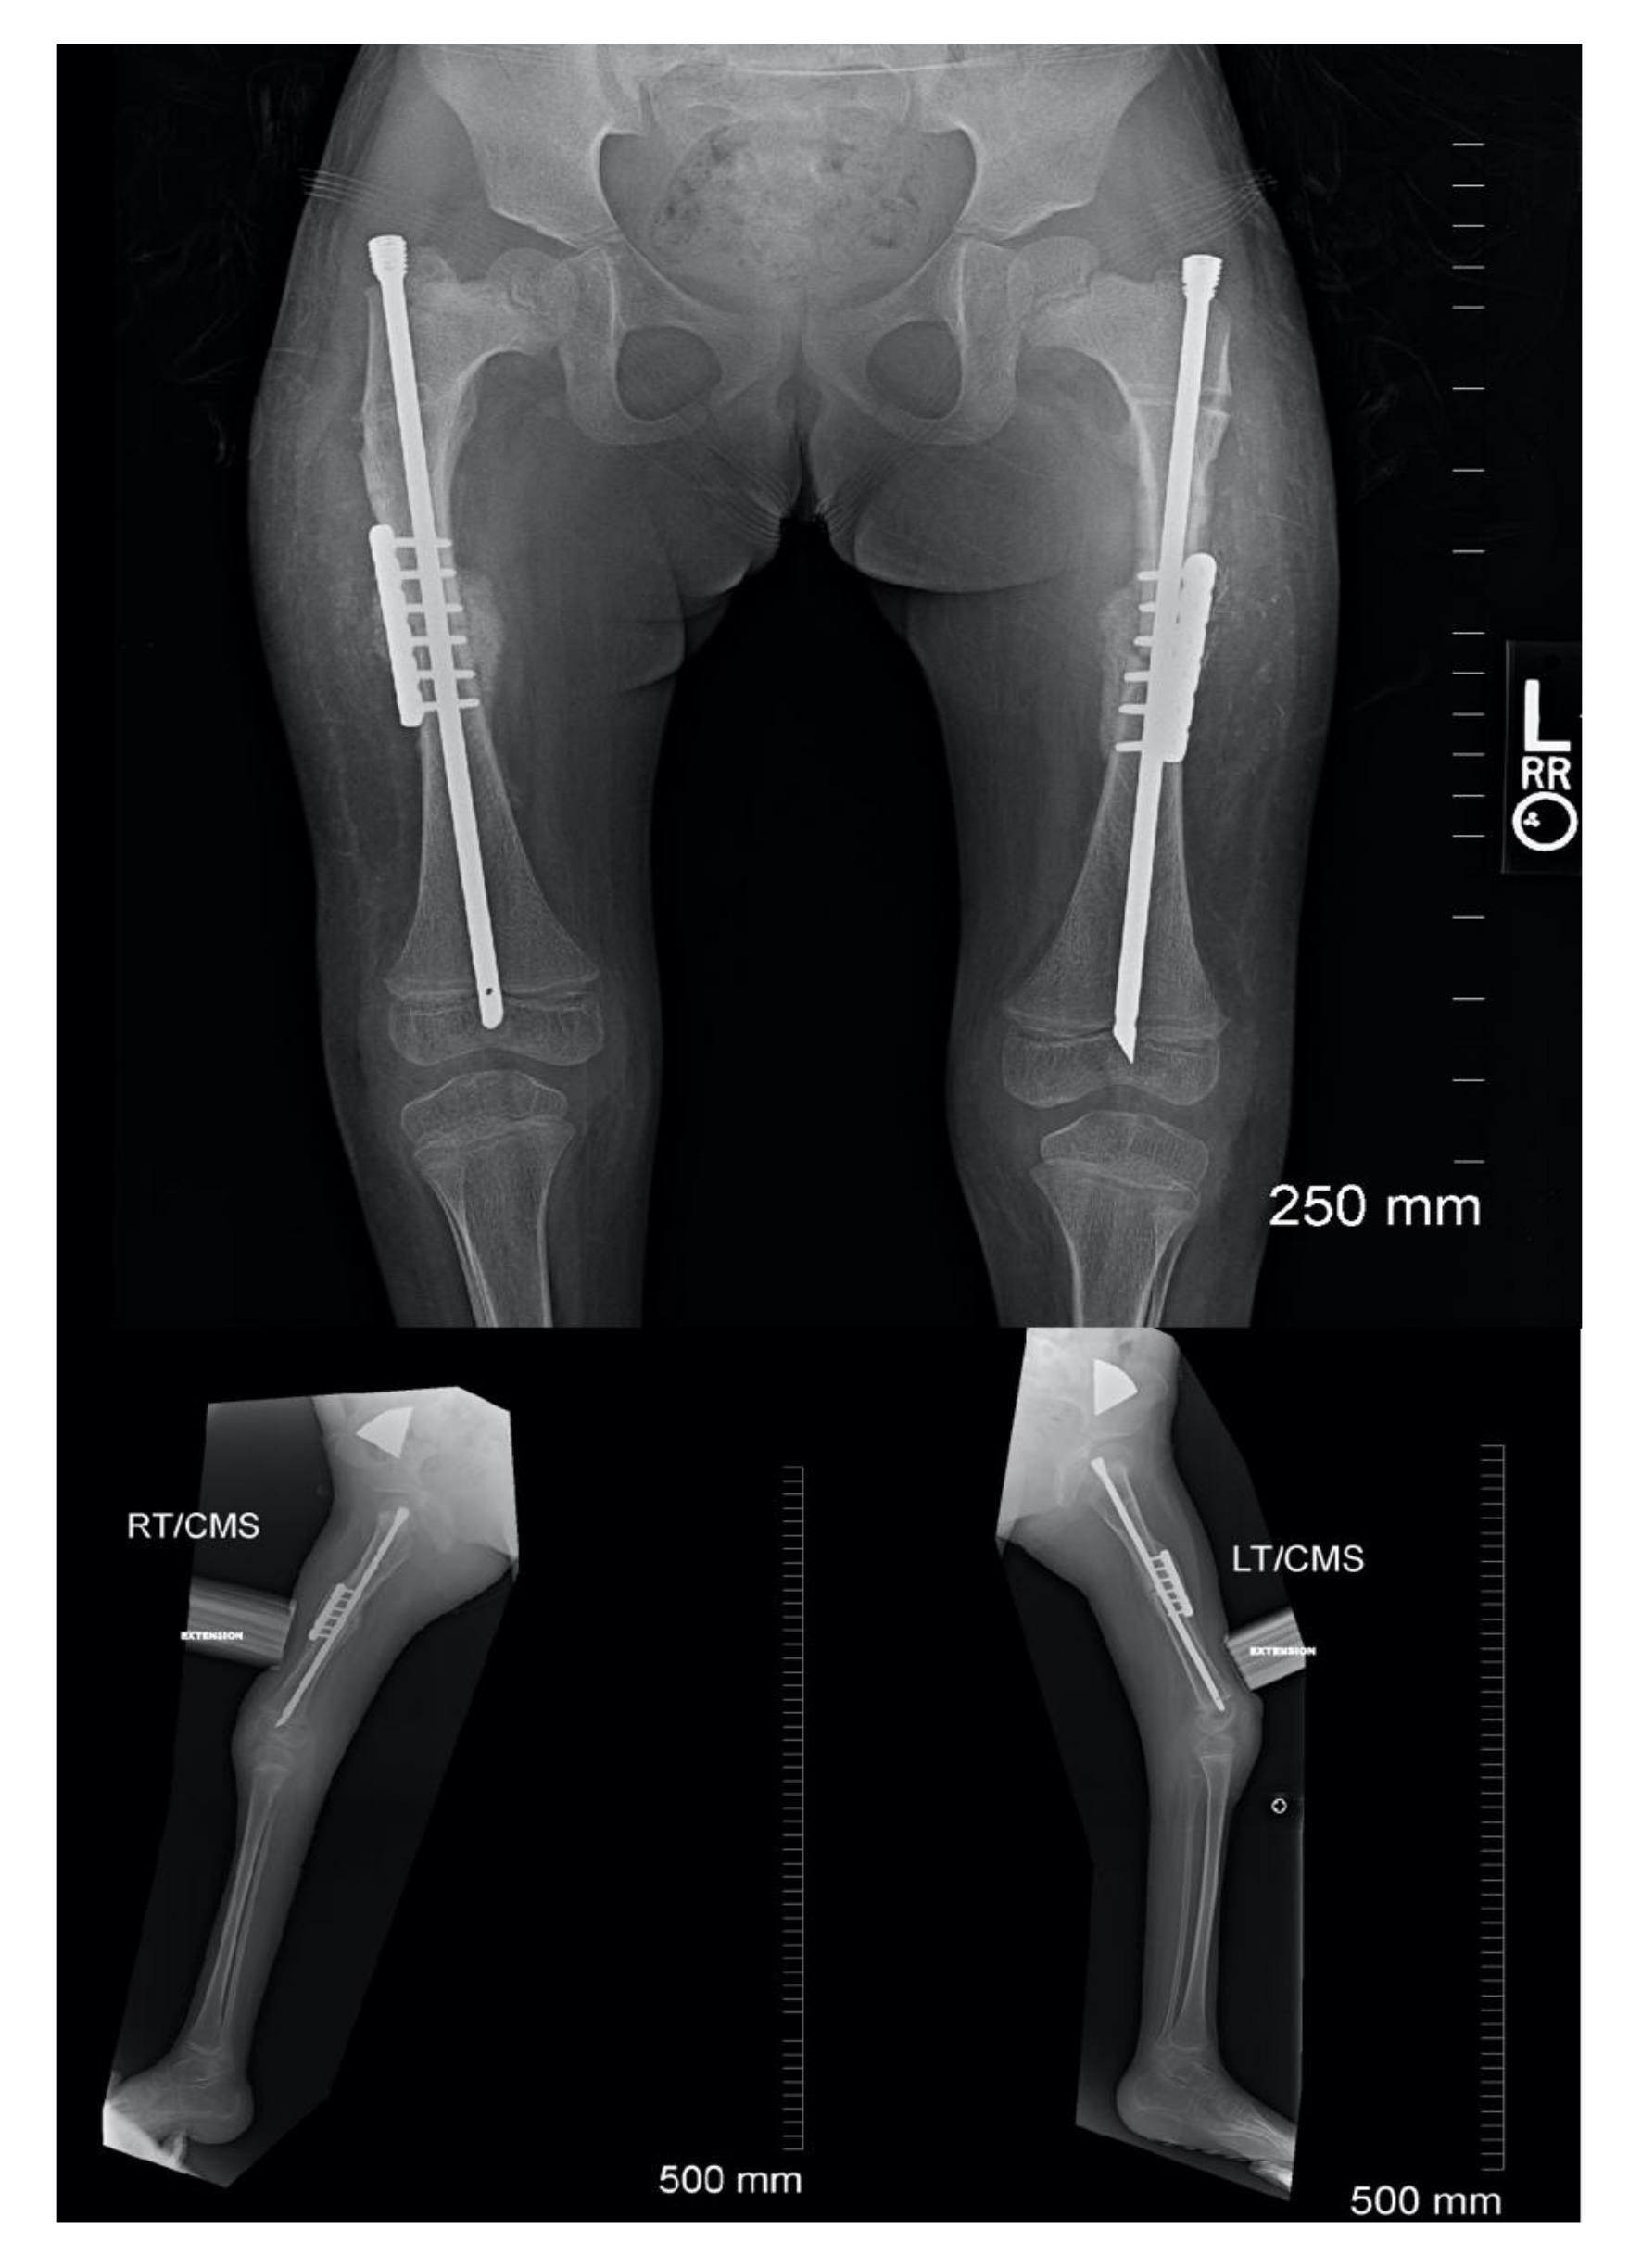

The incision is extended proximally to the subtrochanteric region and the remainder of the proximal femur is subperiosteally dissected. A wire for the appropriate, predetermined, diameter Slim™ rod (Pega Medical, QC, Canada) is inserted from the greater trochanter past the distal femoral physis. The canal is reamed to prepare for placement of the final rod. The length of the rod is determined by measuring the amount of wire in the canal (using another wire and ruler) and subtracting the presumed amount of shortening. For example, if the distance from the greater trochanter to just past the distal femoral physis measures 250 mm and you plan on shortening 50 mm then the rod length should be 200 mm. If the rod length is found to be incorrect, it can be exchanged after shortening osteoplasty. A rotational line is created on the femur with a sagittal saw and the first rod is placed just proximal to the osteotomy site. The osteotomy is performed, and the distal end is delivered out of the wound with a lion jaw. A second rod is placed into the distal femoral segment and into the distal epiphysis of the femur. A 1.8 mm wire is inserted down the canal parallel to the Slim ™ rod into the epiphysis. This is done to protect the physis (Figure 7). Prior to extending the knee the ends of the osteotomy are overlapped to allow shortening and loosening of the soft tissues, particularly the neurovascular bundle. (Figure 7) The knee is extended slowly indirectly releasing adhesions until full extension is obtained. Full extension of the knee is confirmed on a fluoroscopic cross-table lateral (Figure 8), the distal rod and wires are removed, and the overlap of the distal femoral segment to the proximal segment is marked on the distal femoral segment. The femur is shortened the marked amount and should allow for full extension of the knee. This is usually between 3–5 cm but there are times when more may be needed. The proximal rod is inserted into the distal shortened fragment and passed into the epiphysis distally and into the greater trochanter proximally. Rotation is controlled with either a six to eight hole 2.0–2.7 locking plate placed anteriorly or posteriorly to the intramedullary rod (Figure 9). It can be helpful to obtain a lateral fluoroscopic view of the femur to determine optimal plate position relative to the rod. Most often the screws are bicortical. Rotation is checked to be certain that what was once thought to be a rotational deformity may not be. The femoral bone removed from the shortening is ground and used as graft at the osteotomy site. The wound is closed over a 7 mm JP drain.

Figure 9. Post-operative follow-up demonstrating rod and plate construct as well as healing of osteotomy.